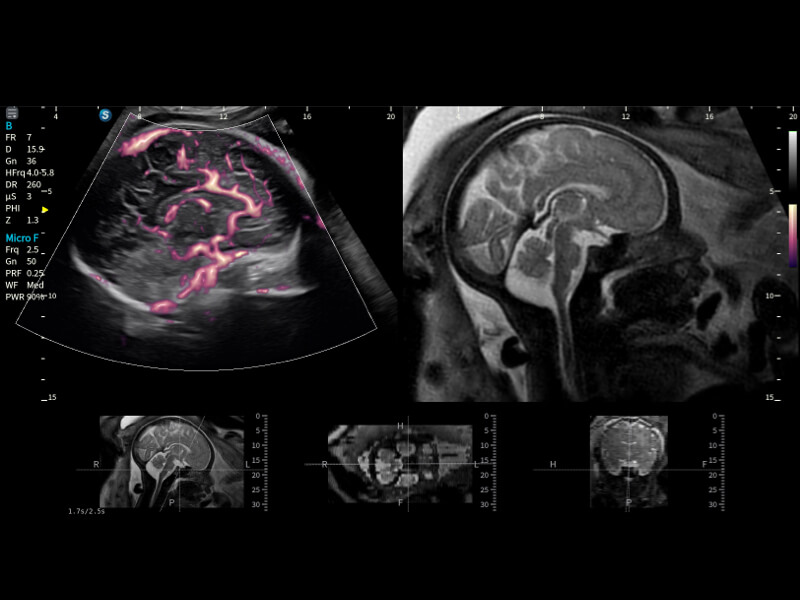

豐富的血流動(dòng)力學(xué)檢測(cè)技術(shù),可在不同醫(yī)療場(chǎng)景中高效捕捉血流信號(hào),助力臨床診療。

在傳統(tǒng)血流的基礎(chǔ)上優(yōu)化掃查和算法策略,能夠更好的抑制組織信息,提煉紅細(xì)胞運(yùn)動(dòng)信息,得到更高幀頻,高靈敏度和分辨率的血流信號(hào),還原更真實(shí)的血流動(dòng)力學(xué)。

通過(guò)光照模型,使二維血流顯示出立體的效果,增加血流的敏感性、成束性,減少外溢。可以和其他不同的血流技術(shù)聯(lián)合使用,融合不同技術(shù)的優(yōu)勢(shì)。輕松應(yīng)對(duì)微小血管,增強(qiáng)血流的立體效果,提升視覺(jué)敏感性。

通過(guò)創(chuàng)新的Matrix E自適應(yīng)濾波算法,能有效濾除軟組織和噪聲信號(hào),最大限度保留超低速微細(xì)血流的信號(hào);結(jié)合超長(zhǎng)時(shí)間域算法,極大提升細(xì)微血流的敏感性和空間分辨率,更真實(shí)的反應(yīng)組織、包塊的血流灌注情況。